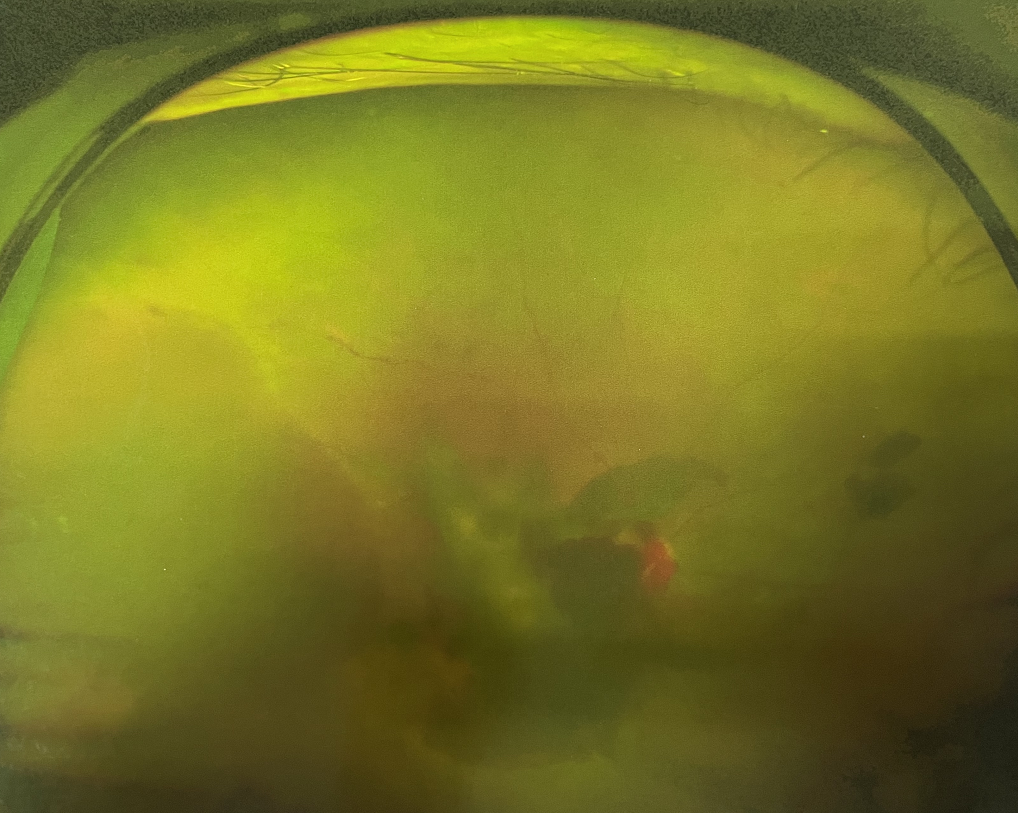

眼底出血多指玻璃體內(nèi),眼睛更深處的視網(wǎng)膜出血。通常情況下,肉眼難以發(fā)現(xiàn)眼底出血,而且發(fā)病初期眼睛也無明顯癥狀,只有借助專業(yè)的眼底檢查儀器才能觀察到異樣。那么眼底出血嚴(yán)重嗎?

眼底出血嚴(yán)重嗎?其中,“三高”患者、高度近視患者和滲出性或濕性老年黃斑變性患者是眼底出血的高發(fā)人群。

醫(yī)生提醒,一旦眼睛出現(xiàn)視力下降、視物變形、視野缺損或眼前有黑影等視覺“異常”的情況,應(yīng)及時到醫(yī)院進(jìn)行眼底檢查,及早發(fā)現(xiàn),及早治療,以免貽誤病情。

眼底出血嚴(yán)重嗎?對于已出現(xiàn)黃斑水腫、視網(wǎng)膜新生血管的患者,根據(jù)眼底血管造影、oct等檢查結(jié)果,給予玻璃體腔注射抗VEGF藥物及激光治療,可以減輕黃斑水腫,使視網(wǎng)膜新生血管消退,以免進(jìn)一步發(fā)生玻璃體出血、視網(wǎng)膜脫離等嚴(yán)重并發(fā)癥的出現(xiàn)。對于玻璃體出血者,傳統(tǒng)認(rèn)為玻璃體出血3-6個月不吸收再進(jìn)行手術(shù)干預(yù),但近年來因為顯微手術(shù)設(shè)備及玻璃體切割技術(shù)已非常成熟,故對于1個月不吸收的玻璃體出血者就可以考慮手術(shù),即手術(shù)時機(jī)應(yīng)該具體情況具體分析,因人而異。